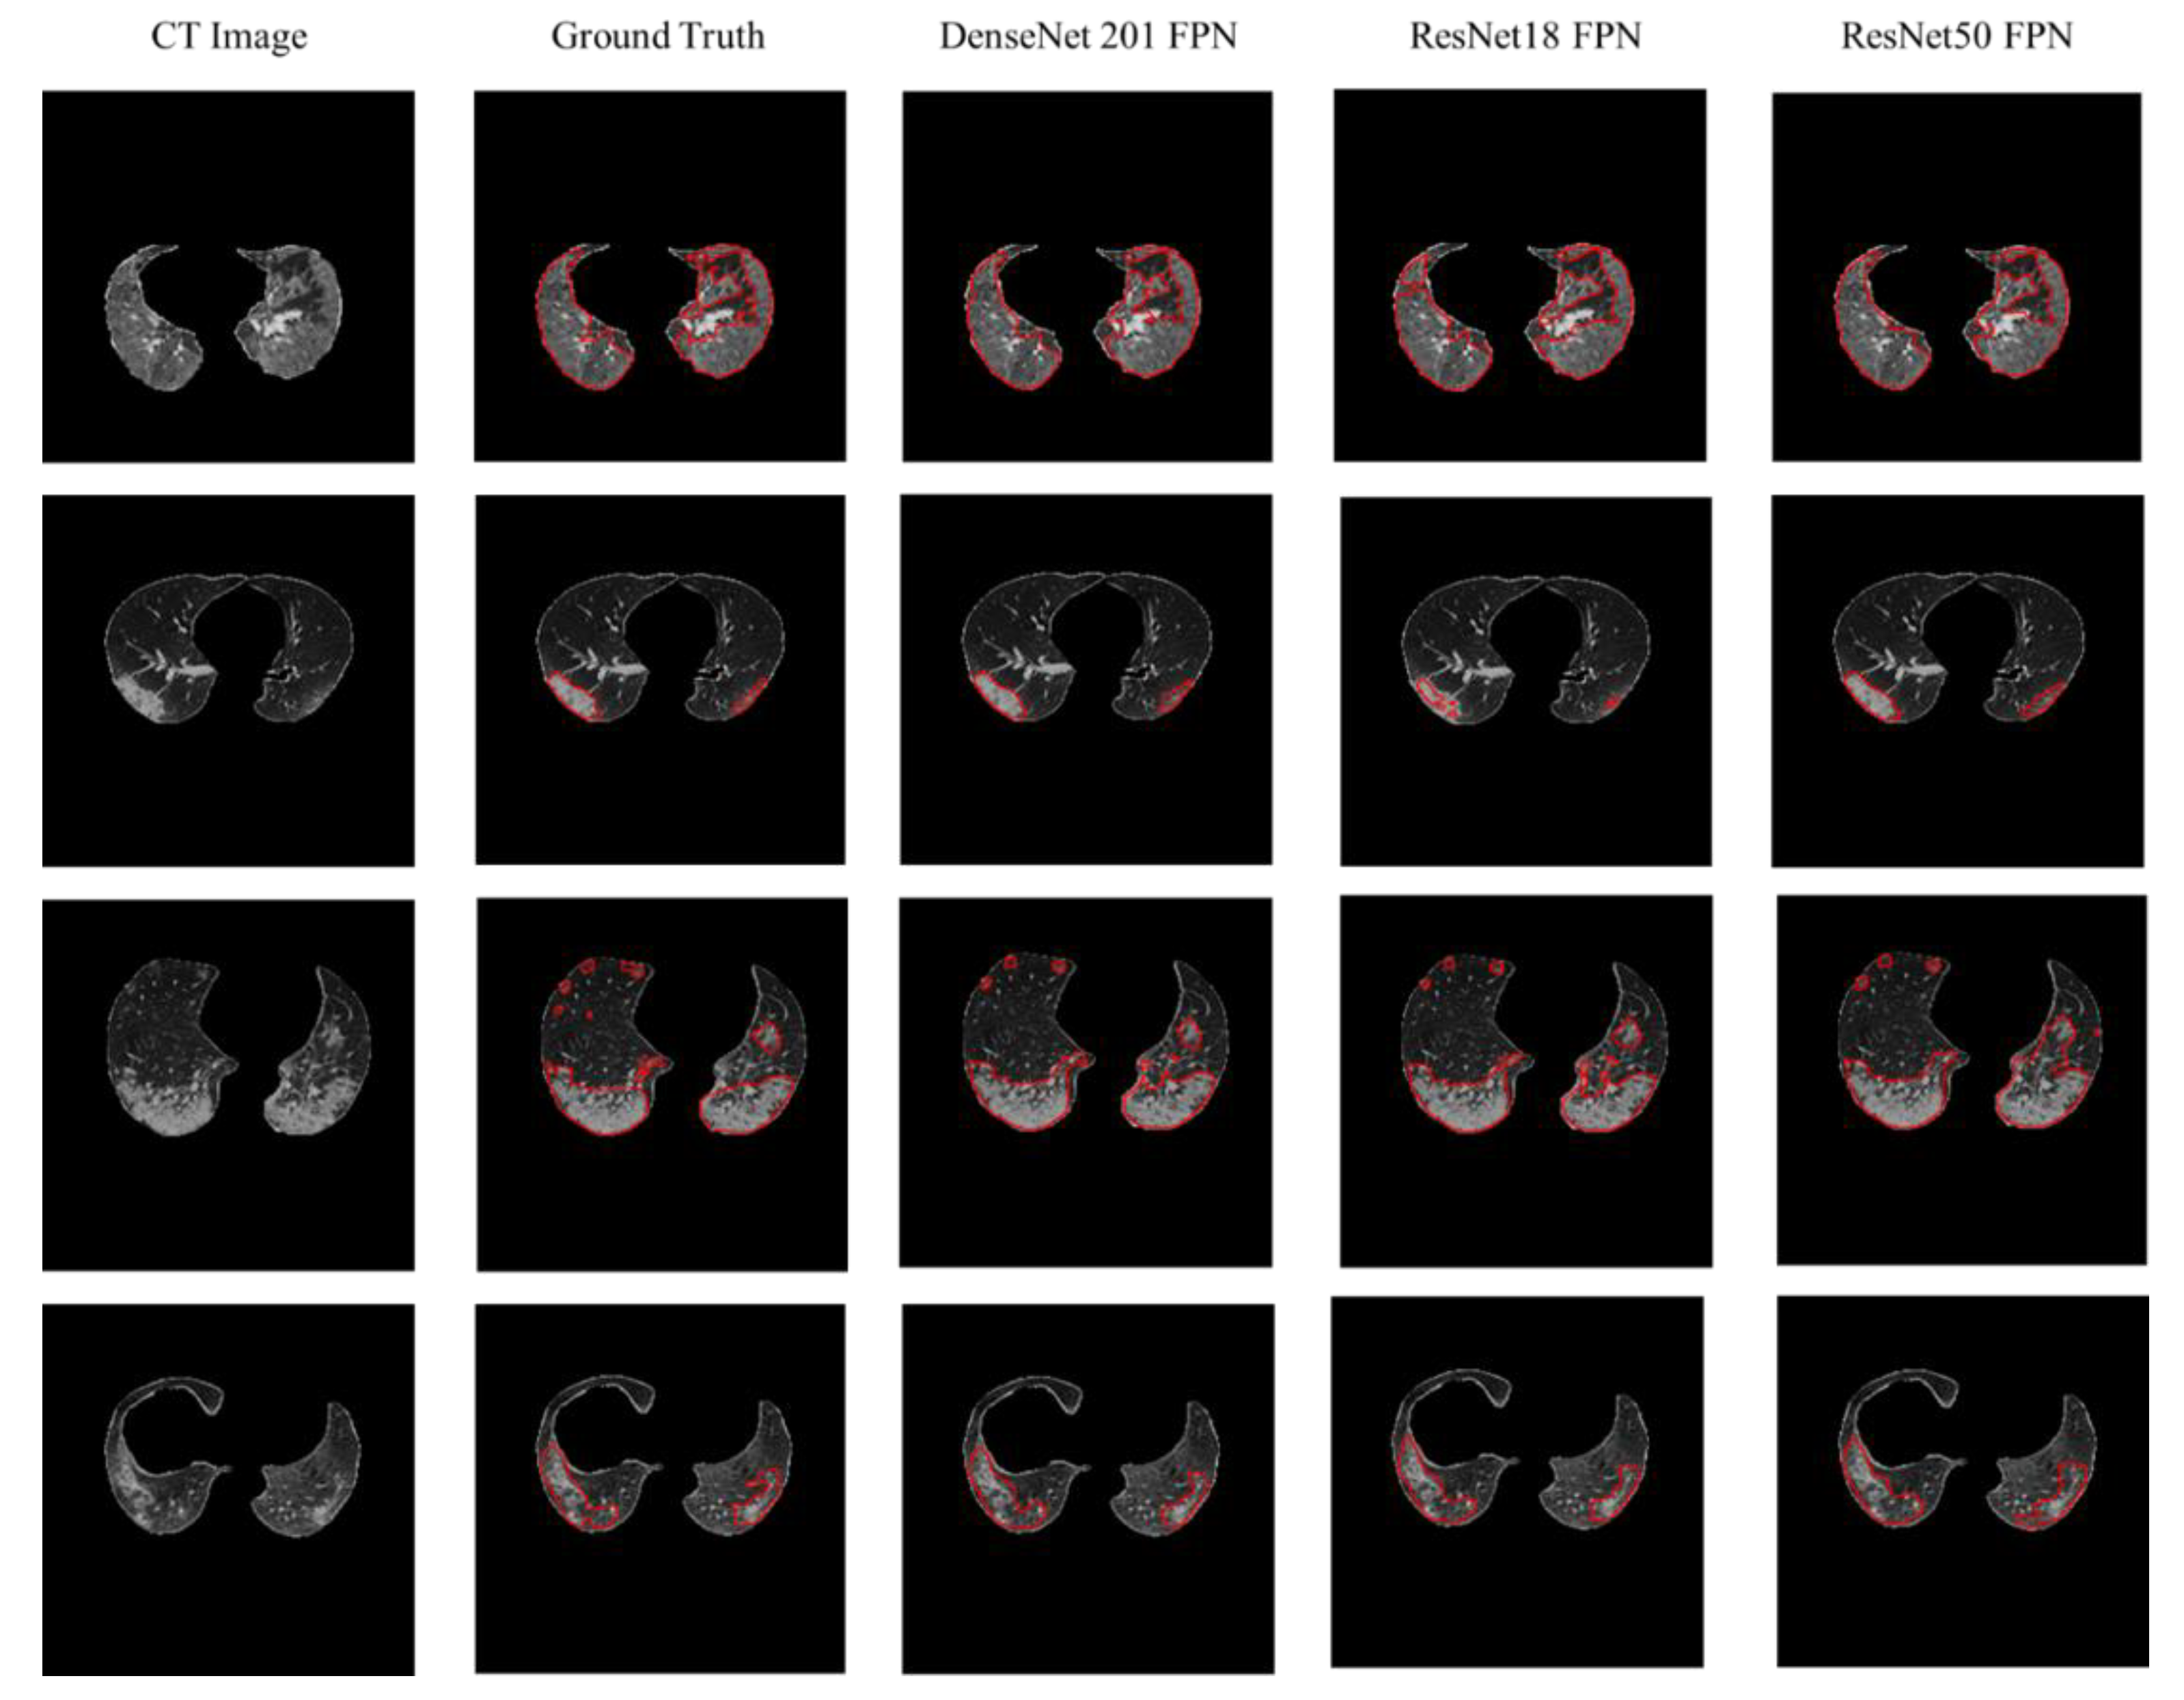

4.2. Lesion Segmentation

| Network | Accuracy (%) | IoU (%) | DSC (%) |

|---|---|---|---|

| UNet | 99.70 ± 0.16 | 95.04 ± 0.63 | 96.61 ± 0.52 |

| ResNet18 UNet | 99.70 ± 0.16 | 95.01 ± 0.63 | 96.84 ± 0.5 |

| ResNet50 UNet | 99.70 ± 0.16 | 95.03 ± 0.63 | 96.8 ± 0.51 |

| ResNet152 UNet | 99.70 ± 0.16 | 94.95 ± 0.63 | 96.69 ± 0.52 |

| DenseNet 121 UNet | 99.70 ± 0.16 | 95.35 ± 0.61 | 97.11 ± 0.48 |

| DenseNet 161 UNet | 99.69 ± 0.16 | 95.10 ± 0.62 | 97.19 ± 0.48 |

| DenseNet 201 UNet | 94.88 ± 0.64 | 94.88 ± 0.64 | 97.00 ± 0.49 |

| ResNet18 FPN | 99.65 ± 0.17 | 93.6 ± 0.71 | 95.76 ± 0.58 |

| ResNet50 FPN | 99.65 ± 0.17 | 93.39 ± 0.72 | 95.52 ± 0.6 |

| ResNet152 FPN | 99.66 ± 0.17 | 93.92 ± 0.69 | 96.00 ± 0.57 |

| DenseNet 121 FPN | 99.67 ± 0.16 | 94.53 ± 0.66 | 96.55 ± 0.53 |

| DenseNet 161 FPN | 99.66 ± 0.17 | 94.05 ± 0.68 | 96.11 ± 0.56 |

| DenseNet t201 FPN | 99.67 ± 0.17 | 94.35 ± 0.67 | 96.39 ± 0.54 |